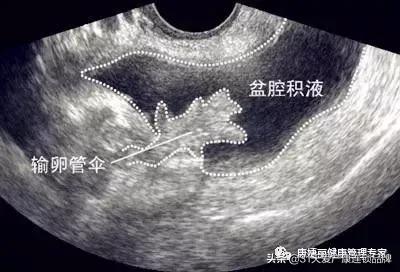

盆腔积液是指对盆腔内液体这一表现的一种描述。可分为生理性盆腔积液和病理性盆腔积液。先来说说生理性盆腔积液。

盆腔处于腹腔最低部,当盆腹腔脏器有少量渗出液、漏出液时,液体会先聚积在盆腔,从而形成盆腔积液。